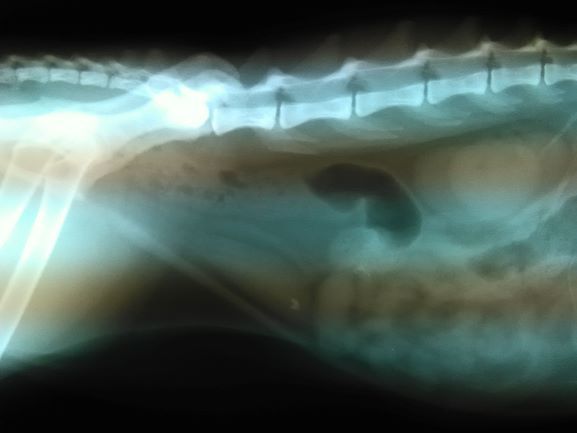

Röntgen und Ultraschall liefern uns die richtigen Antworten bei vielen Fragen und helfen so Krankheiten zu diagnostizieren und zu therapieren.

Röntgen des Brustraumes (Herz, Lunge etc.)

Röntgen des Bauchraumes (Magen-Darmtrakt, Leber, Milz, Blase etc.)